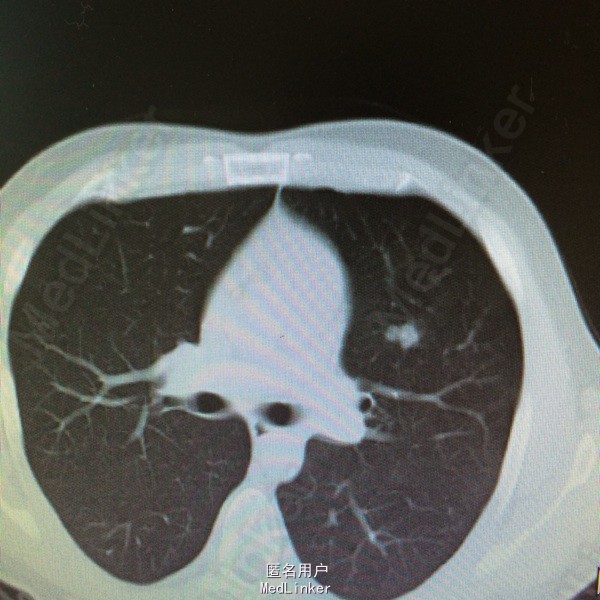

患者因“鼻咽癌放疗后2年余,双肺多发转移治疗后复发2周”入院。详见图片

查体一般可,生命体征平稳,双颈部等浅表未及明显肿大淋巴结,2015.9.15复查ct提示两肺多发转移瘤,较前增多增大。

鼻咽癌肺转移,拟予全身化疗

患者鼻咽癌肺多发转移,目前鼻咽部及双颈部CR,双肺多发转移后予全身化疗及全肺姑息性放疗,放疗后全肺缓解期8个月,未见肺炎。放疗后复发予全身化疗,化疗后缓解期约3个月,现再次复发,但患者血象不宜全身化疗,讨论治疗方案